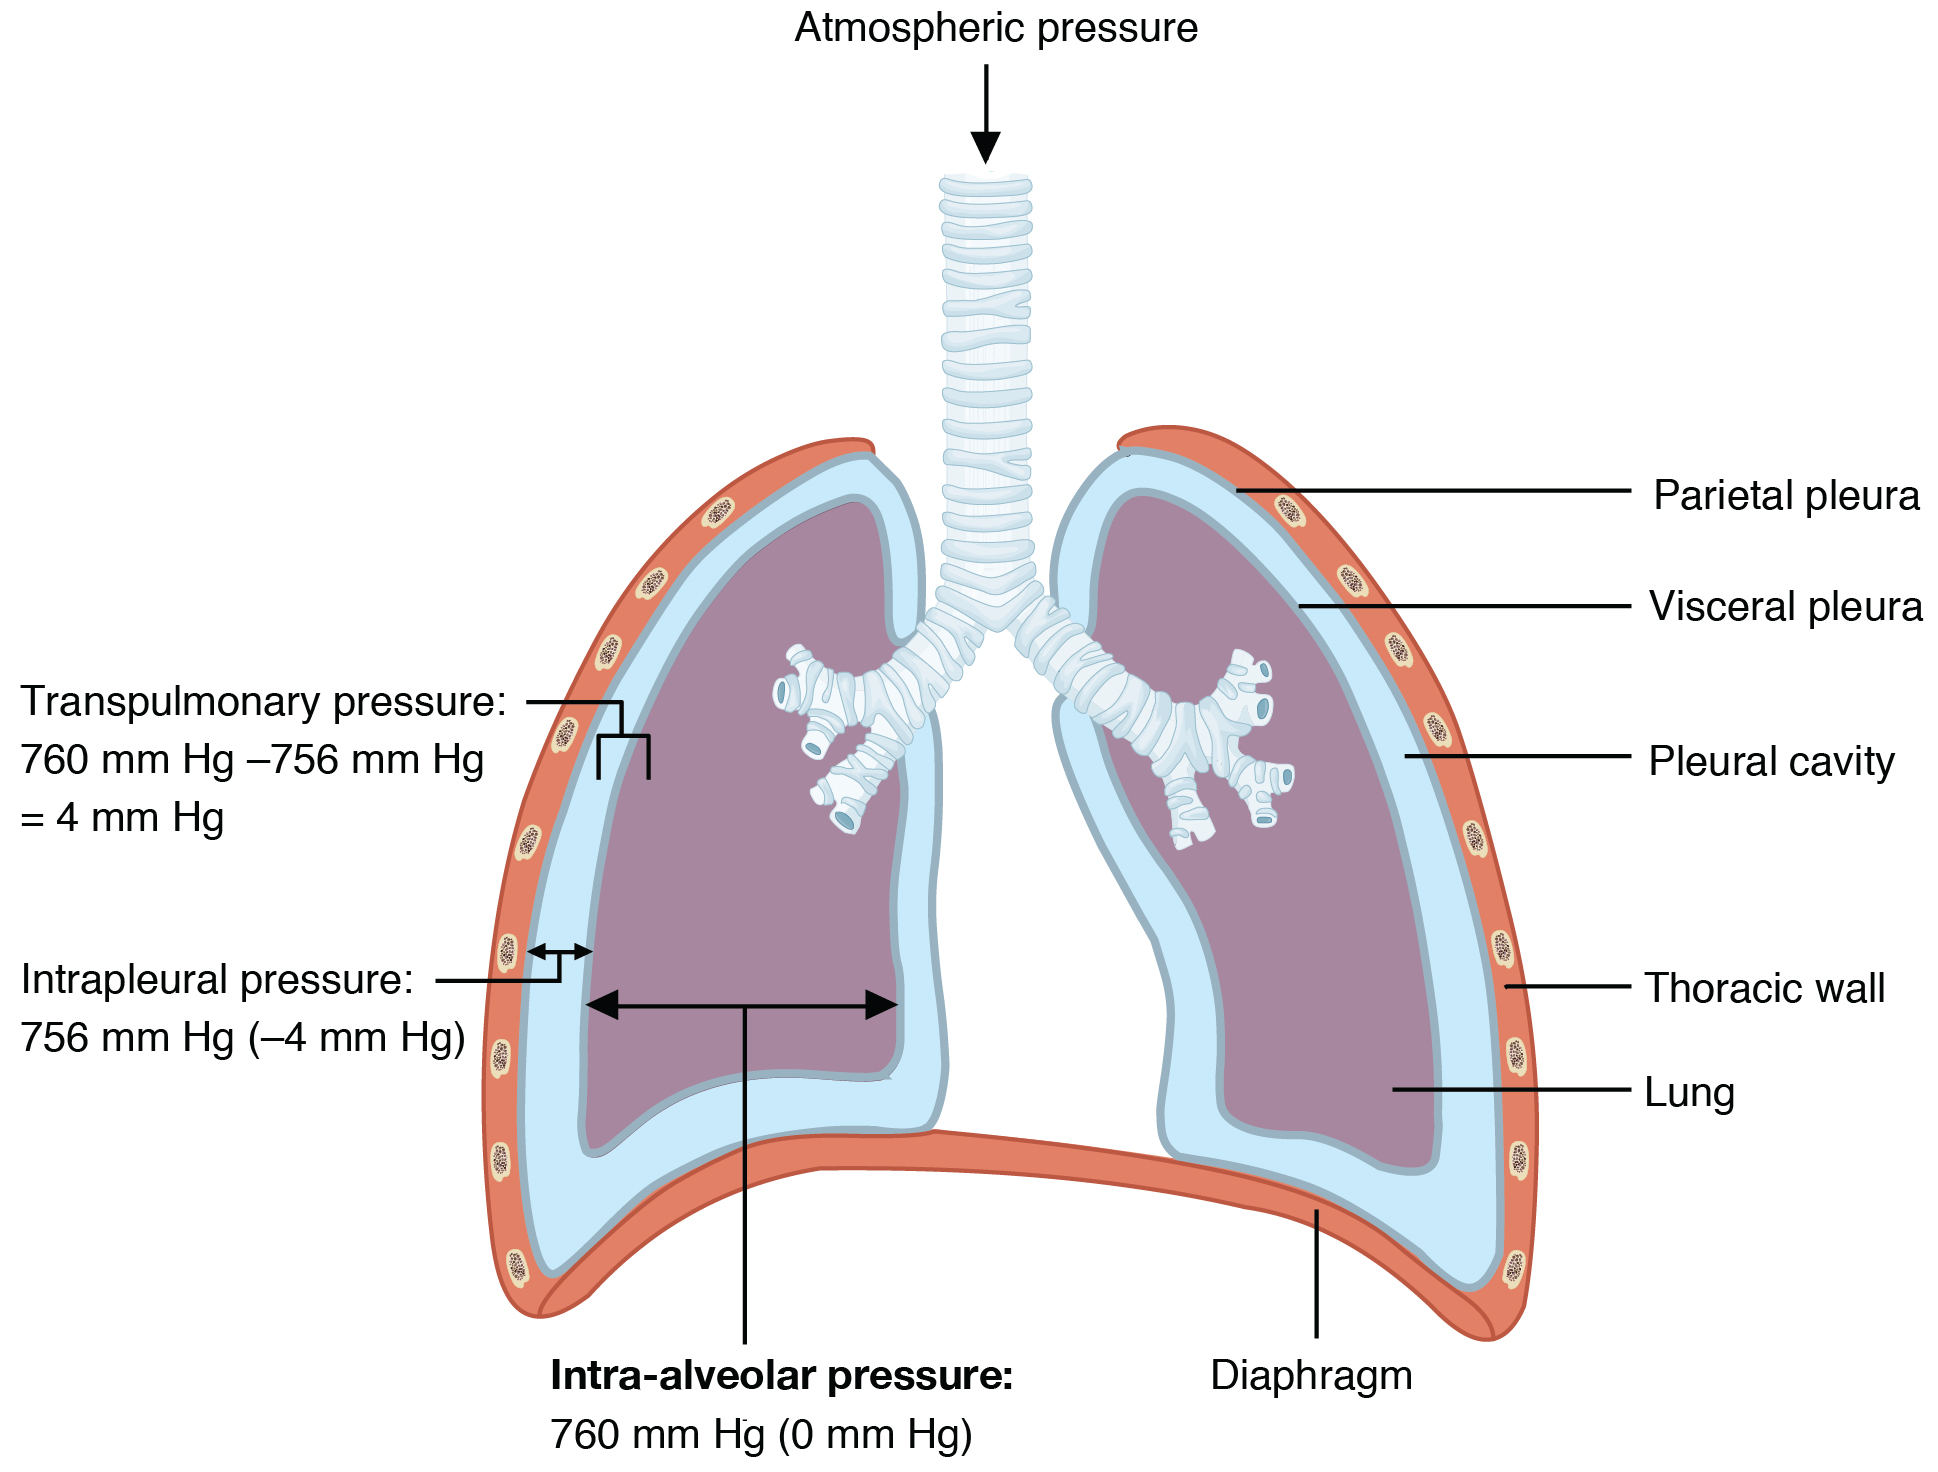

Respiratory failure is a critical condition that develops due to low blood-oxygen levels in the bloodstream that makes involuntary tasks like breathing almost impossible to do on your own. The low blood-oxygen levels results due to inadequate gas exchange during pulmonary circulation, which could be because of pump failure or lung failure. Pump failure is a ventilation failure which causes hypercapnia whereas lung failure is gas exchange failure causing hypoxemia. It can also de defined as arterial oxygen tension (Pao2 < 60mmHg) or arterial carbon dioxide tension (PaCO2).

Type I: – involves a ventilation/perfusion mismatch that causes untreatable hypoxemia (PaO2). Another characteristic of type I respiratory failure is alveolar flooding.

Type II: – involves alveolar hypoventilation resulting in hypercapnia (PaCO2). There is a significant reduction in the alveolar minute ventilation that entails inadequate removal of carbon dioxide.

Type III: – type III respiratory failure usually takes place in the peri or post operative period where the abdominal wall mechanics are abnormal. Patients usually have progressive atelectasis due to inadequate functional residual capacity leads to . The clinical progression of type III respiratory failure usually leads to either type I or type II respiratory failure.